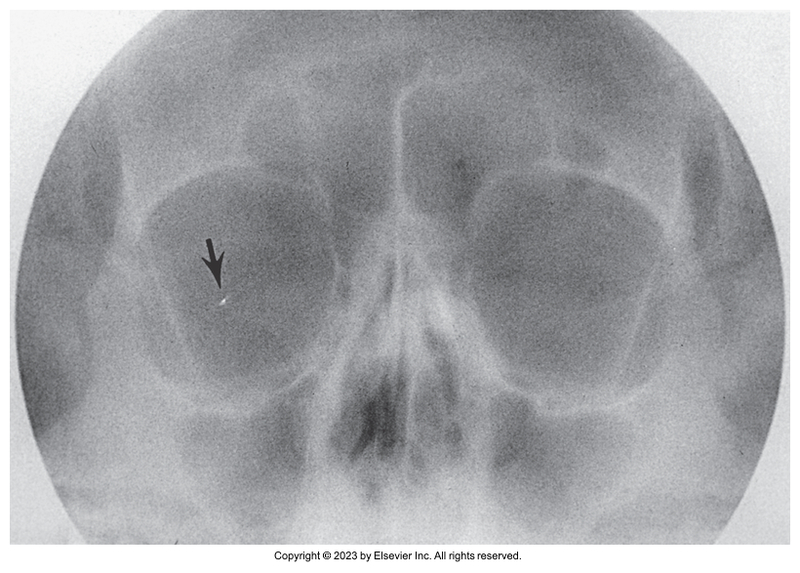

Parietoacanthial of the orbits - Modified Waters Method

Parietoacanthial of orbits - Modified waters method